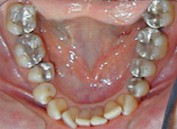

Electrogalvanismo en boca

producido por el asentamiento de la prótesis de cromo cobalto sobre

amalgamas |

Al examen

clínico intraoral observamos coronas de porcelana con pequeños sobrecontornos en

sus márgenes y radiográficamente presenta postes metálicos cónicos.

Rx en la que se observa los postes metálicos |

Rehabilitación realizada en el 2001 |